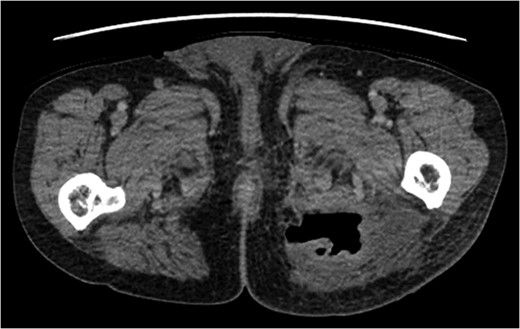

A rare complication of diverticular disease is the formation of fistulas, most commonly either colo-vesical or colo-vaginal. We present the unusual case of a perforated sigmoid diverticulum forming a colo-gluteal fistula and presenting initially as a gluteal abscess in an otherwise asymptomatic patient. After drainage of the gluteal abscess, the patient re-presented with faecal loss from the abscess drainage site. Imaging revealed fistulous communication between the sigmoid and the left obturator internus muscle, tracking to the gluteus maximus with associated abscess and cutaneous communication to the site of previous drainage. The patient underwent an emergency Hartmann's procedure with lay open/abscess drainage of the gluteal cavity. Post-operatively the patient experienced continuing discharge from the gluteal fistula despite repeated drainage and debridement causing considerable morbidity, inconvenience and misery. Clinicians should maintain a high index of suspicion when presented with a gluteal abscess and should consider the possibility of an intra-abdominal source.

The patient re-presented a week after discharge, complaining off persistent pain around the buttock, with feculent discharge and flatulence from the wound. Abscess cultures from the previous admission were reviewed and noted to have grown Escherichia coli and clostridium species.

An emergency Hartmann's procedure was performed under general anaesthetic through a lower midline incision as well as lay open of the perineal fistula. On opening the abdomen, a perforated diverticulum was identified extending into the left lateral pelvic wall. A standard Hartmann's procedure was performed, with sigmoid colectomy, division of rectum at recto-sigmoid junction and a tension-free stoma formed in left hypochondrium. The left buttock abscess cavity extended by a further 2–3 in. and the cavity then packed.

Following the operation, the patient had a short and uncomplicated critical care stay and was subsequently discharged. He has since continued to experience ongoing discharge from the fistula with follow-up imaging showing a reduction in the size of the abscess cavity but continuing patency of the fistula tract, despite repeated wound debridement and packing, drainage of the fistula and rectal washout.